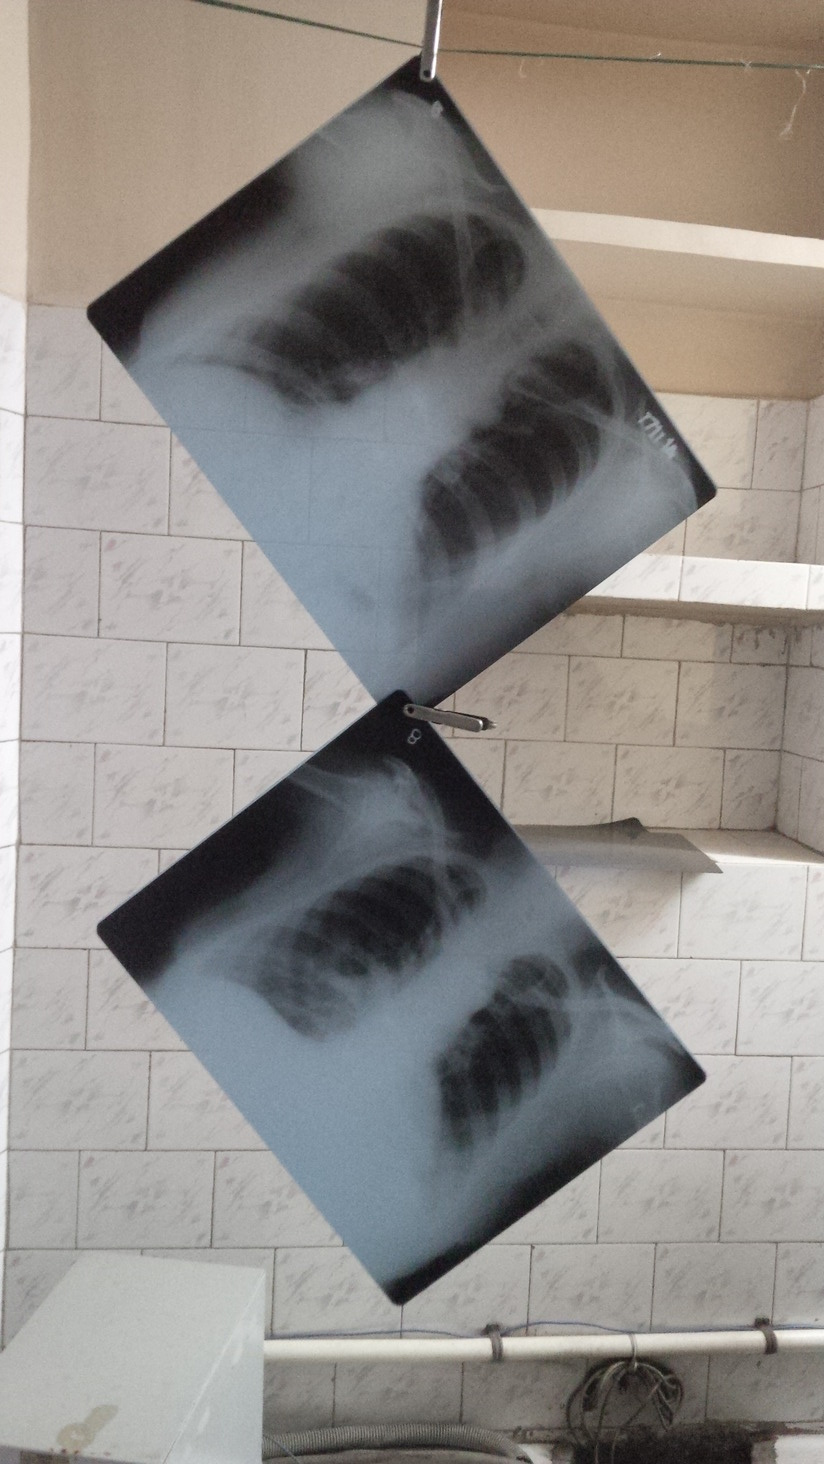

Chest radiography in tuberculosis detection

On 14th December, the World Health Organization (WHO) released a consolidated summary of WHO recommendations on the use chest radiography (CXR) in TB detection and guidance on programmatic approaches to use CXR within primary care services. WHO underscores the importance of CXR an essential tool for the early detection of TB, and therefore fundamental to achieve the targets set out in WHO’s End TB Strategy.